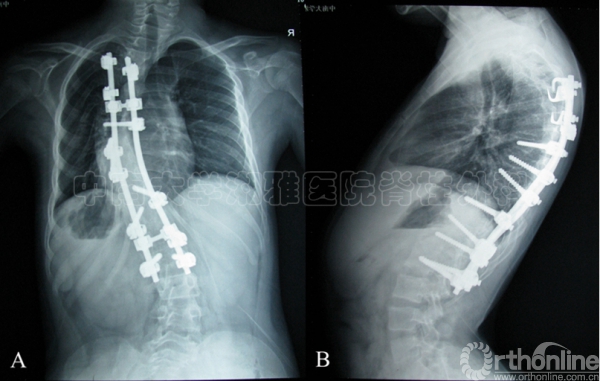

A-B:一期行后颅窝减压,蛛网膜粘连松解术,二期行后路钉棒矫形内固定植骨融合术后1年上端椎脱钩,出现PJK46°。

C-D:翻修术中相

E-F:予以后路翻修术,延长了固定节段,PJK改善明显。